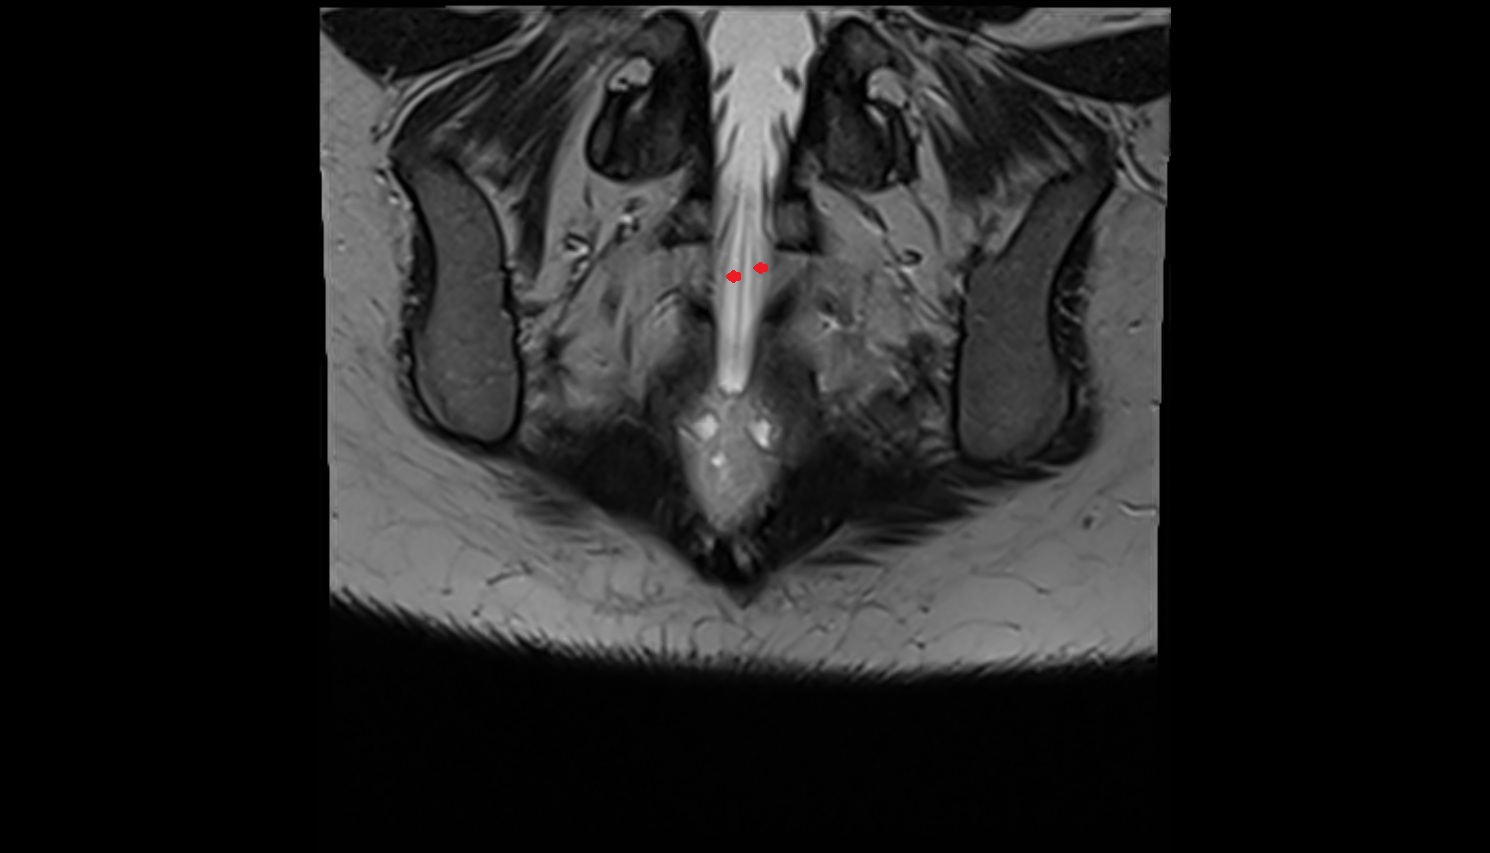

- Peripheral zone of prostate

- Anterior Fibromuscular Stroma of prostate

- Central zone of prostate

- Transitional zone of prostate